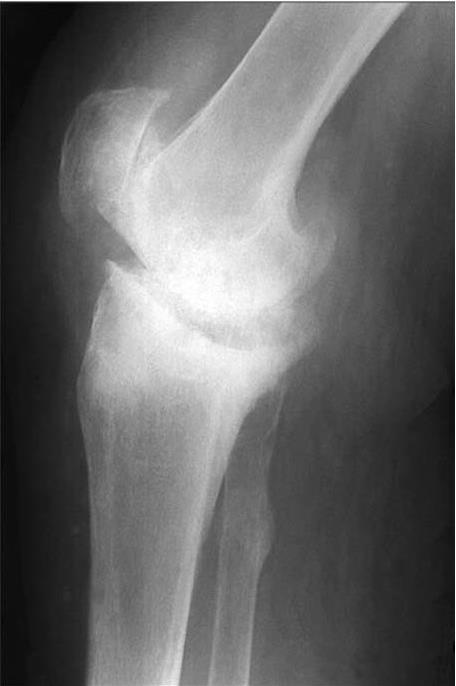

Рис. 18. Рентгенограмма коленного сустава больного, IV стадия РА

На боковой проекции рентгенограммы обращает на себя внимание отсутствие суставной щели. Костные балки прорастают в смежные отделы сустава